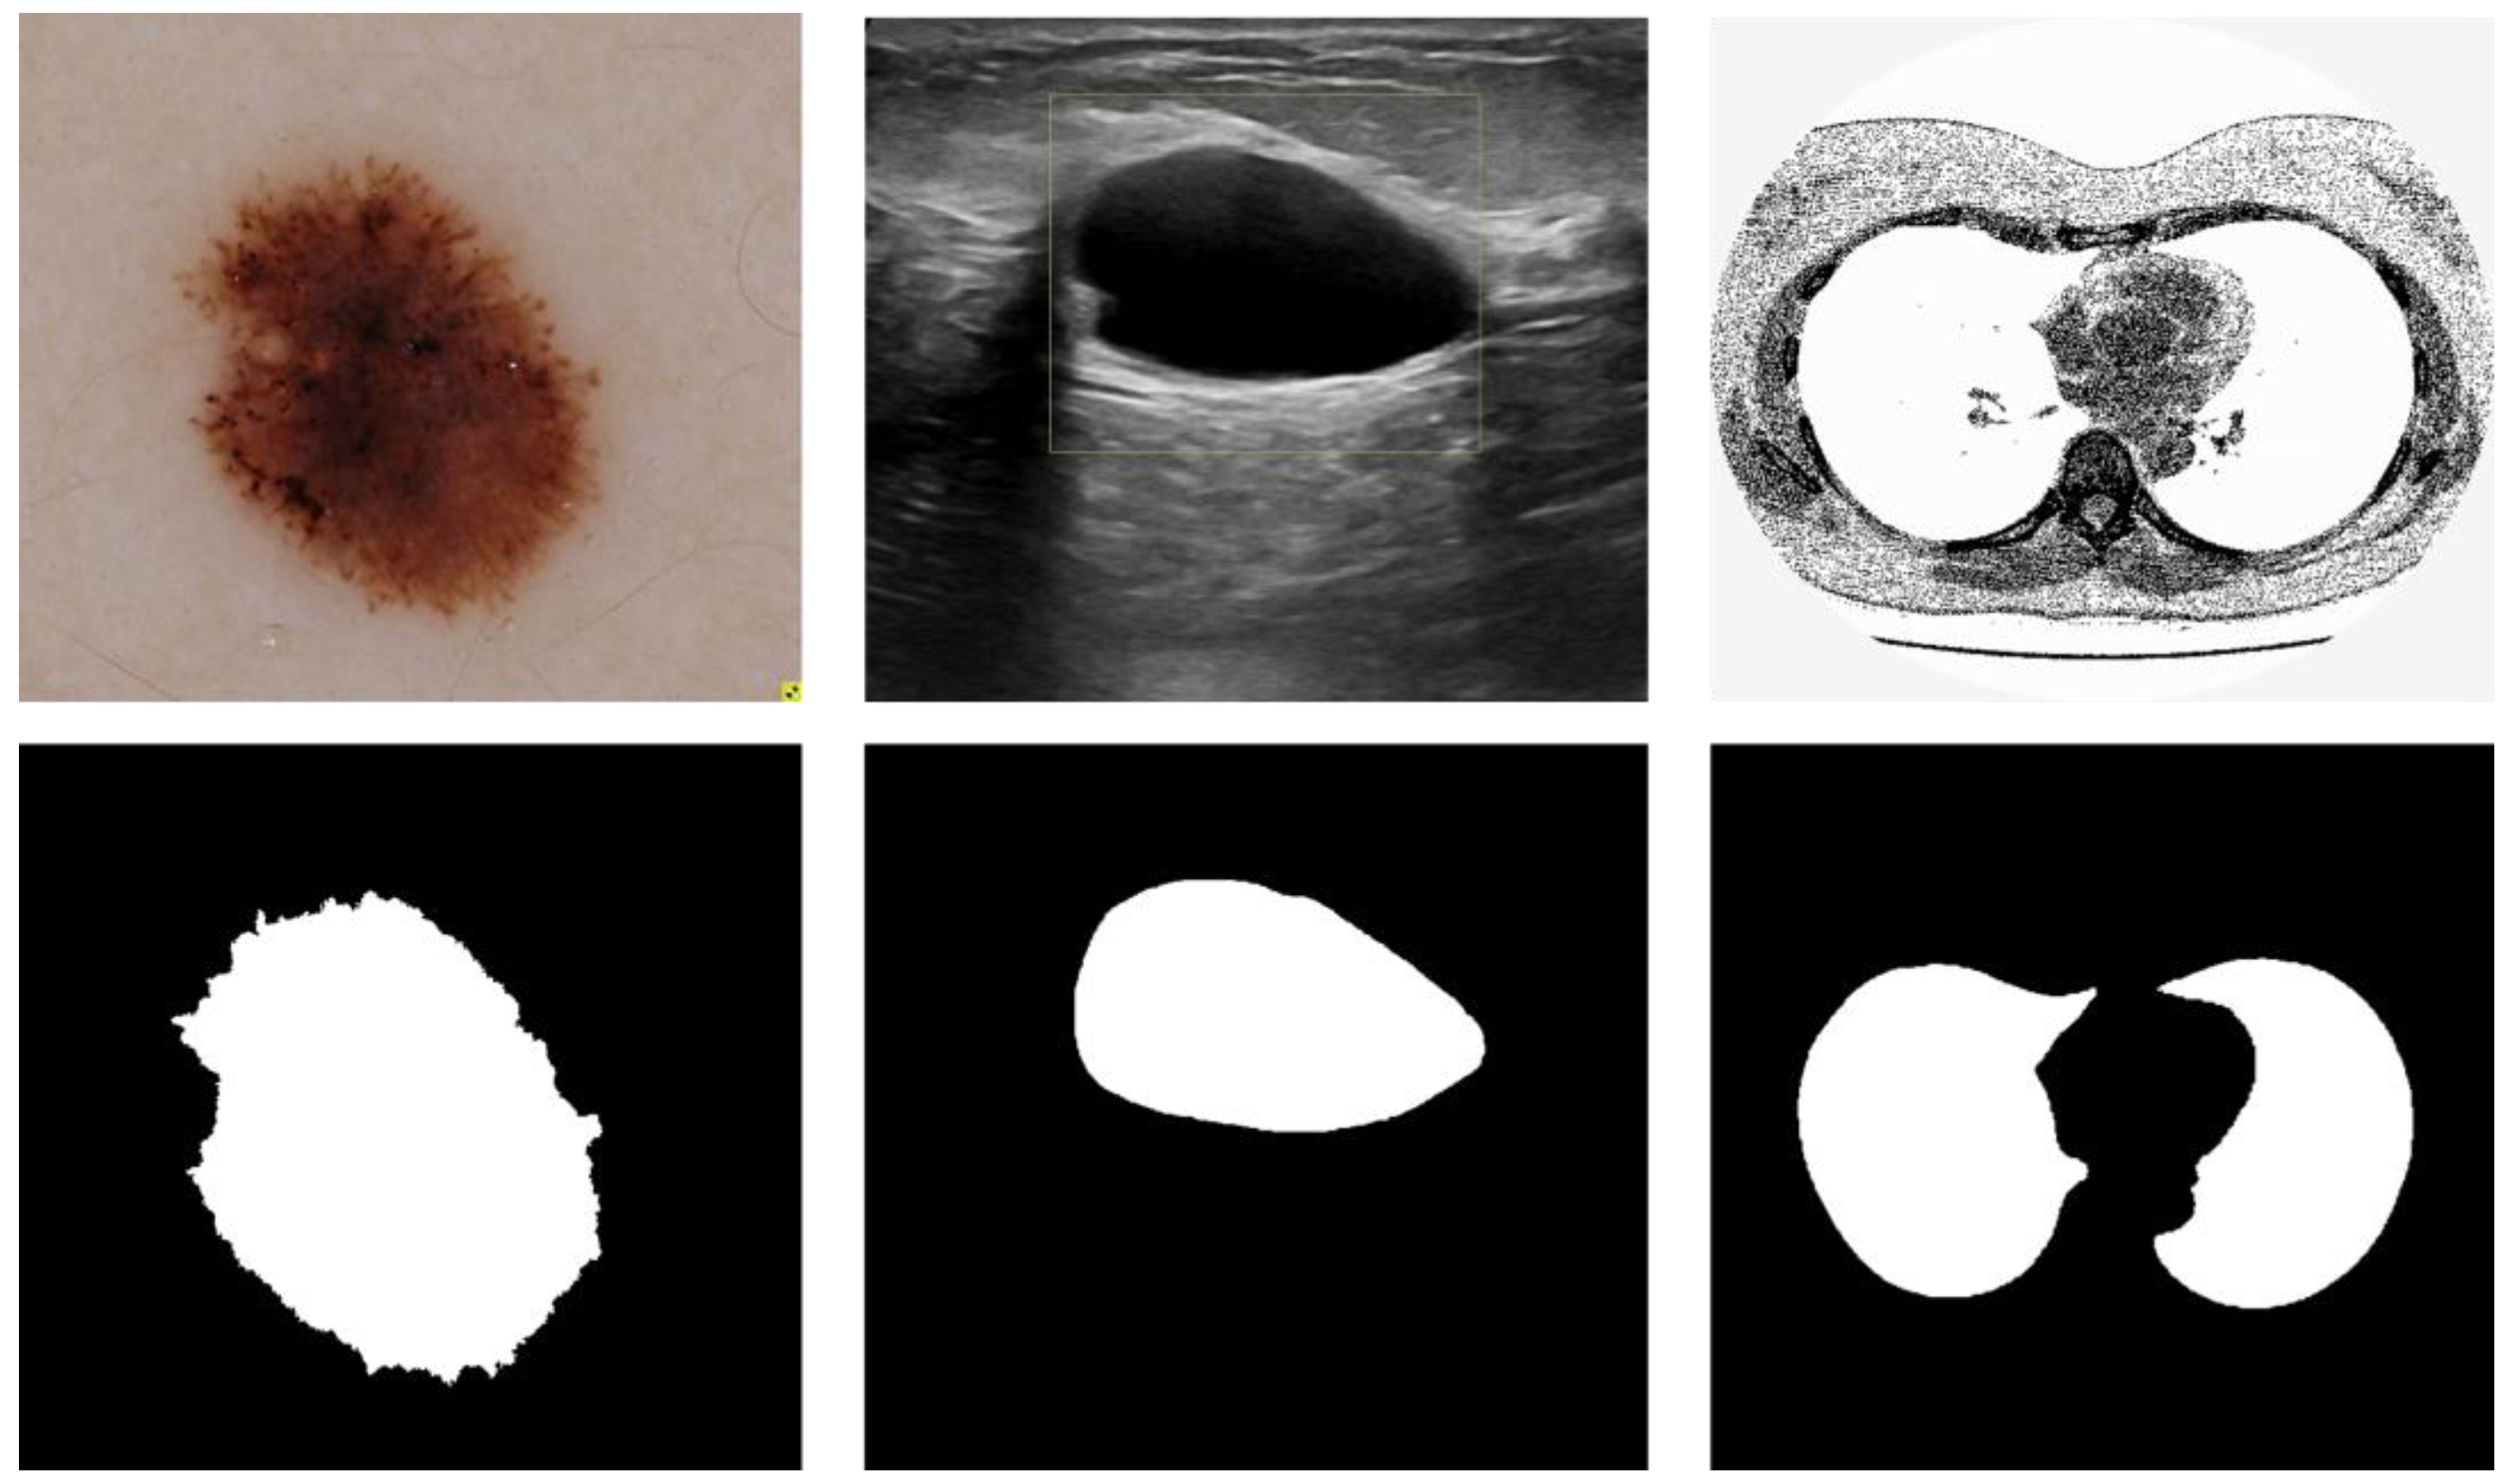

3.6. Visual Analysis

This section shows the partial visual segmentation results of the three datasets of skin, breast, and lung segmentation, as shown in Figure 10, Figure 11 and Figure 12, respectively. The segmentation results of each method are image binarized with a threshold of 0.5 [28]. Firstly, the presented methods are sharper in boundary segmentation in the skin image, comparable to GT pictures. Secondly, all methods’ segmentation results are not perfect in the breast image, but Ref-UNet 3+ and CBAM+Ref-Unet 3+ can accurately find the lesion. Lastly, in the lung image, the segmentation accuracy of each model was higher, but our models performed the best in handling details.

Figure 3. Medical image segmentation: skin cancer lesion segmentation on the left, breast cancer segmentation, and lung segmentation on the right.

Figure 10. Visualization of skin cancer segmentation results. From left to right: original image, ground truth, segmentation result of Unet, segmentation result of Unet 3+, segmentation result of Ref-Unet 3+, and segmentation result of CBAM+Ref-Unet 3+.

Diagnostics 13 00576 g010

Figure 11. Visualization of breast cancer segmentation results. From left to right: original image, ground truth, segmentation result of Unet, segmentation result of Unet 3+, segmentation result of Ref-Unet 3+, and segmentation result of CBAM+Ref-Unet 3+.

Diagnostics 13 00576 g011

Figure 12. Visualization of lung segmentation results. From left to right: original image, ground truth, segmentation result of Unet, segmentation result of Unet 3+, segmentation result of Ref-Unet 3+, and segmentation result of CBAM+Ref-Unet 3+.

Diagnostics 13 00576 g012